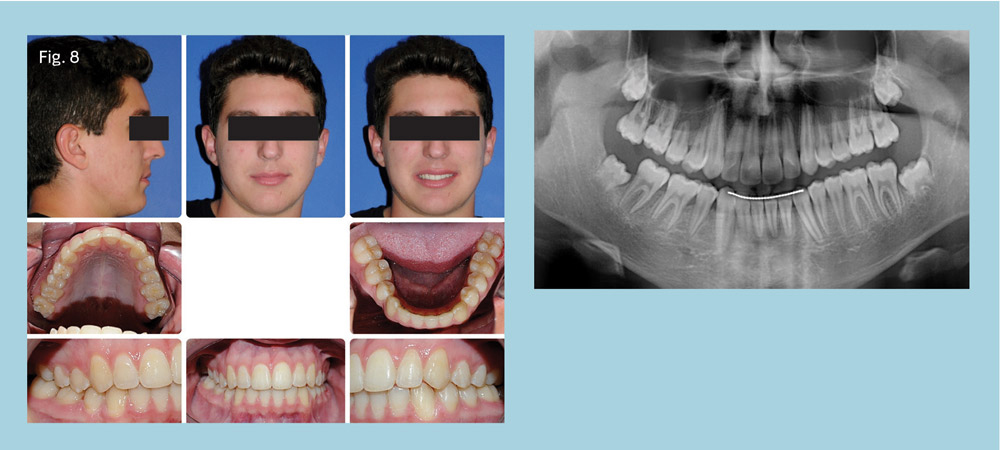

The family's chief complaint was addressed and an excellent occlusion was achieved while maintaining good dental and facial esthetics. The patient and his family were very pleased with the outcome. The vertical defects on teeth #28 and #30 were greatly improved and satisfactory root parallelism was achieved (Fig. 8).

Class I canine and full-cusp Class III molar occlusion were achieved on the right, and Class I occlusion on the left. The patient finished with ideal overjet, and the midlines were coincident.

Treatment time was 28 months, but five months passed between the time the patient was referred for extraction of the ankylosed tooth T and when the TAD was placed. Thus, active treatment time was closer to 23 months.

Conclusion